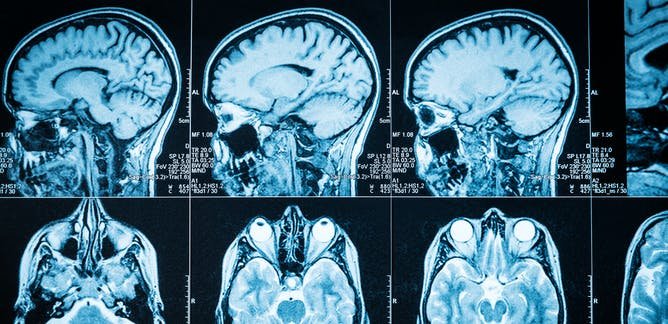

20-year-old Sydney student suffers permanent brain damage & can no longer walk properly post her Pfizer jab in September. Her distraught parents tell her story: